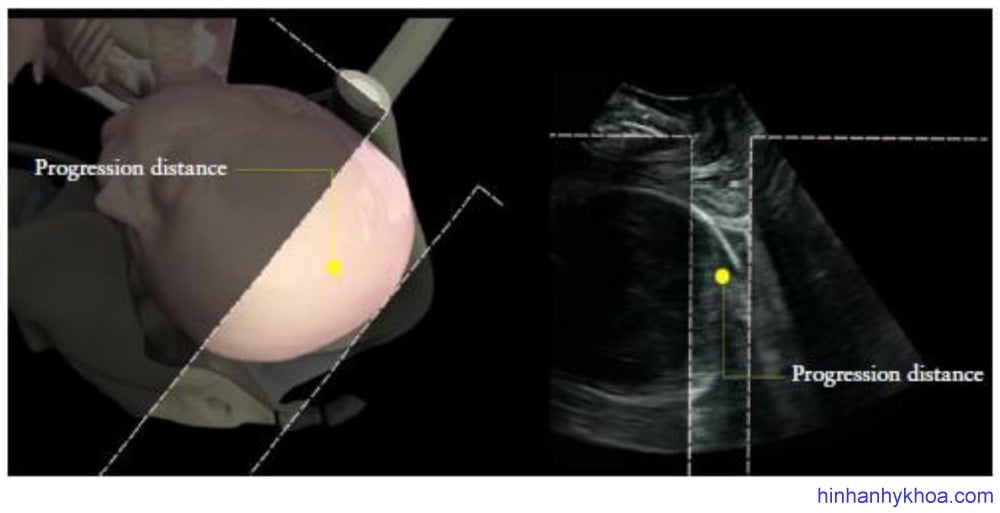

PD được mô tả đầu tiên bởi Dietz và Lanzarone30, là khoảng cách ngắn nhất giữa đường dưới mu và phần bản sọ xa nhất của đầu thai (Hình 9). Bởi vì AoP dễ đo lường hơn PD và còn kết hợp giải thích được độ cong tự nhiên của ống sanh, trong khi PD thì không, do đó AoP được ưa thích hơn để đo lường độ lọt thai.

Hình 9: Cách đo khoảng cách tiến triển (PD)